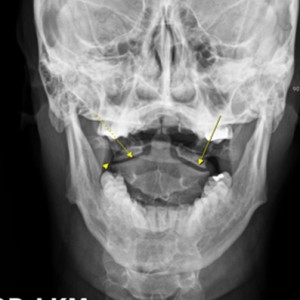

안면 두개골 엑스레이 검사

Submento Vertex View 포함

안면 두개골 CT

경추 1,2번의 변위 파악

턱관절 검사에 전신 척추를 촬영·검사하는 이유가 무엇인가요?

턱관절과 척추가 신체 정렬과 기능에 밀접하게 연결되어 있기 때문입니다. 턱관절 문제는 목뼈를 포함한 척추 정렬에 영향을 미치며, 이는 전신적인 불균형을 초래할 수 있습니다. 또한 턱관절과 척추는 근육 및 신경계를 통해 상호작용하므로, 턱관절 이상은 목과 어깨는 물론 척추 전체에도 연쇄적인 영향을 미칠 가능성이 있습니다. 전신 척추 촬영은 턱관절 문제의 정확한 원인을 파악하고, 자세와 정렬의 이상을 분석하여 근본적인 치료 전략을 세우기 위해 필수적입니다.